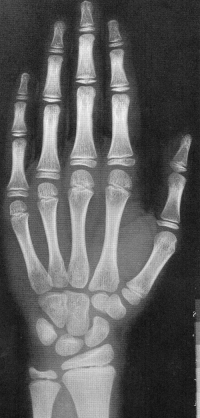

Sexo Masculino

14 anos